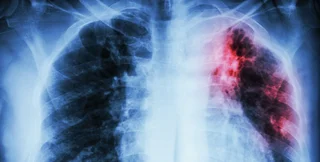

ТОЛЬКО НЕ ЭТО. Из-за недостатка информации люди воспринимают диагноз "туберкулез" как приговор